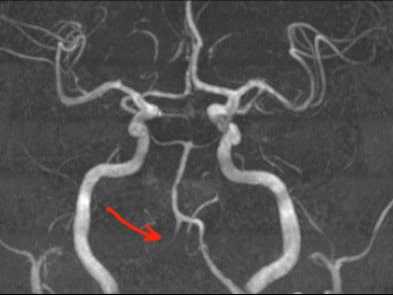

Магнитно-резонансная томография (МРТ) позволяет оценить состояние головного мозга, наличие свежих и старых ишемических очагов. В режиме МРТ ангиографии возможно без контраста оценить состояние шейных и внутримозговых отделов позвоночных артерий. С точки зрения визуализации артериальной патологии МРА уступает компьютерной томографии с ангиографией, однако не требует использовани контрастного вещества, что важно для пациентов с нарушением функции почек. На представленном изображении показана тромботическая закупорка левой позвоночной артерии (отсутствие контрастирование показано стрелкой).